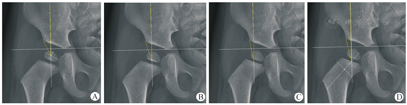

以髋臼顶的外侧骨缘为CEA测量髋臼侧标志点,将骨化核在长度和宽度上一分为二的两条线的交界定义为骨化核的中心,将骨化核靠近骨骺一侧的中点定义为骨化核骨骺侧中点,将股骨近端干骺端平台的中点定义为骨骺连线的中点,将股骨近端干骺端边线与分隔股骨颈的中线的交界定义为骨骺连线与股骨颈中线交叉点。本研究4种测量方法分别以上述4点作为股骨头中心标志点,测量所得的CEA分别简称为骨化核中心CEA、骨化核骨骺侧中点CEA、骨骺连线中点CEA、骨骺连线与股骨颈中线交叉点CEA(图1)。

注:图中两条黄线所夹的角为不同股骨头中心代替标志点测量的中心边缘角。